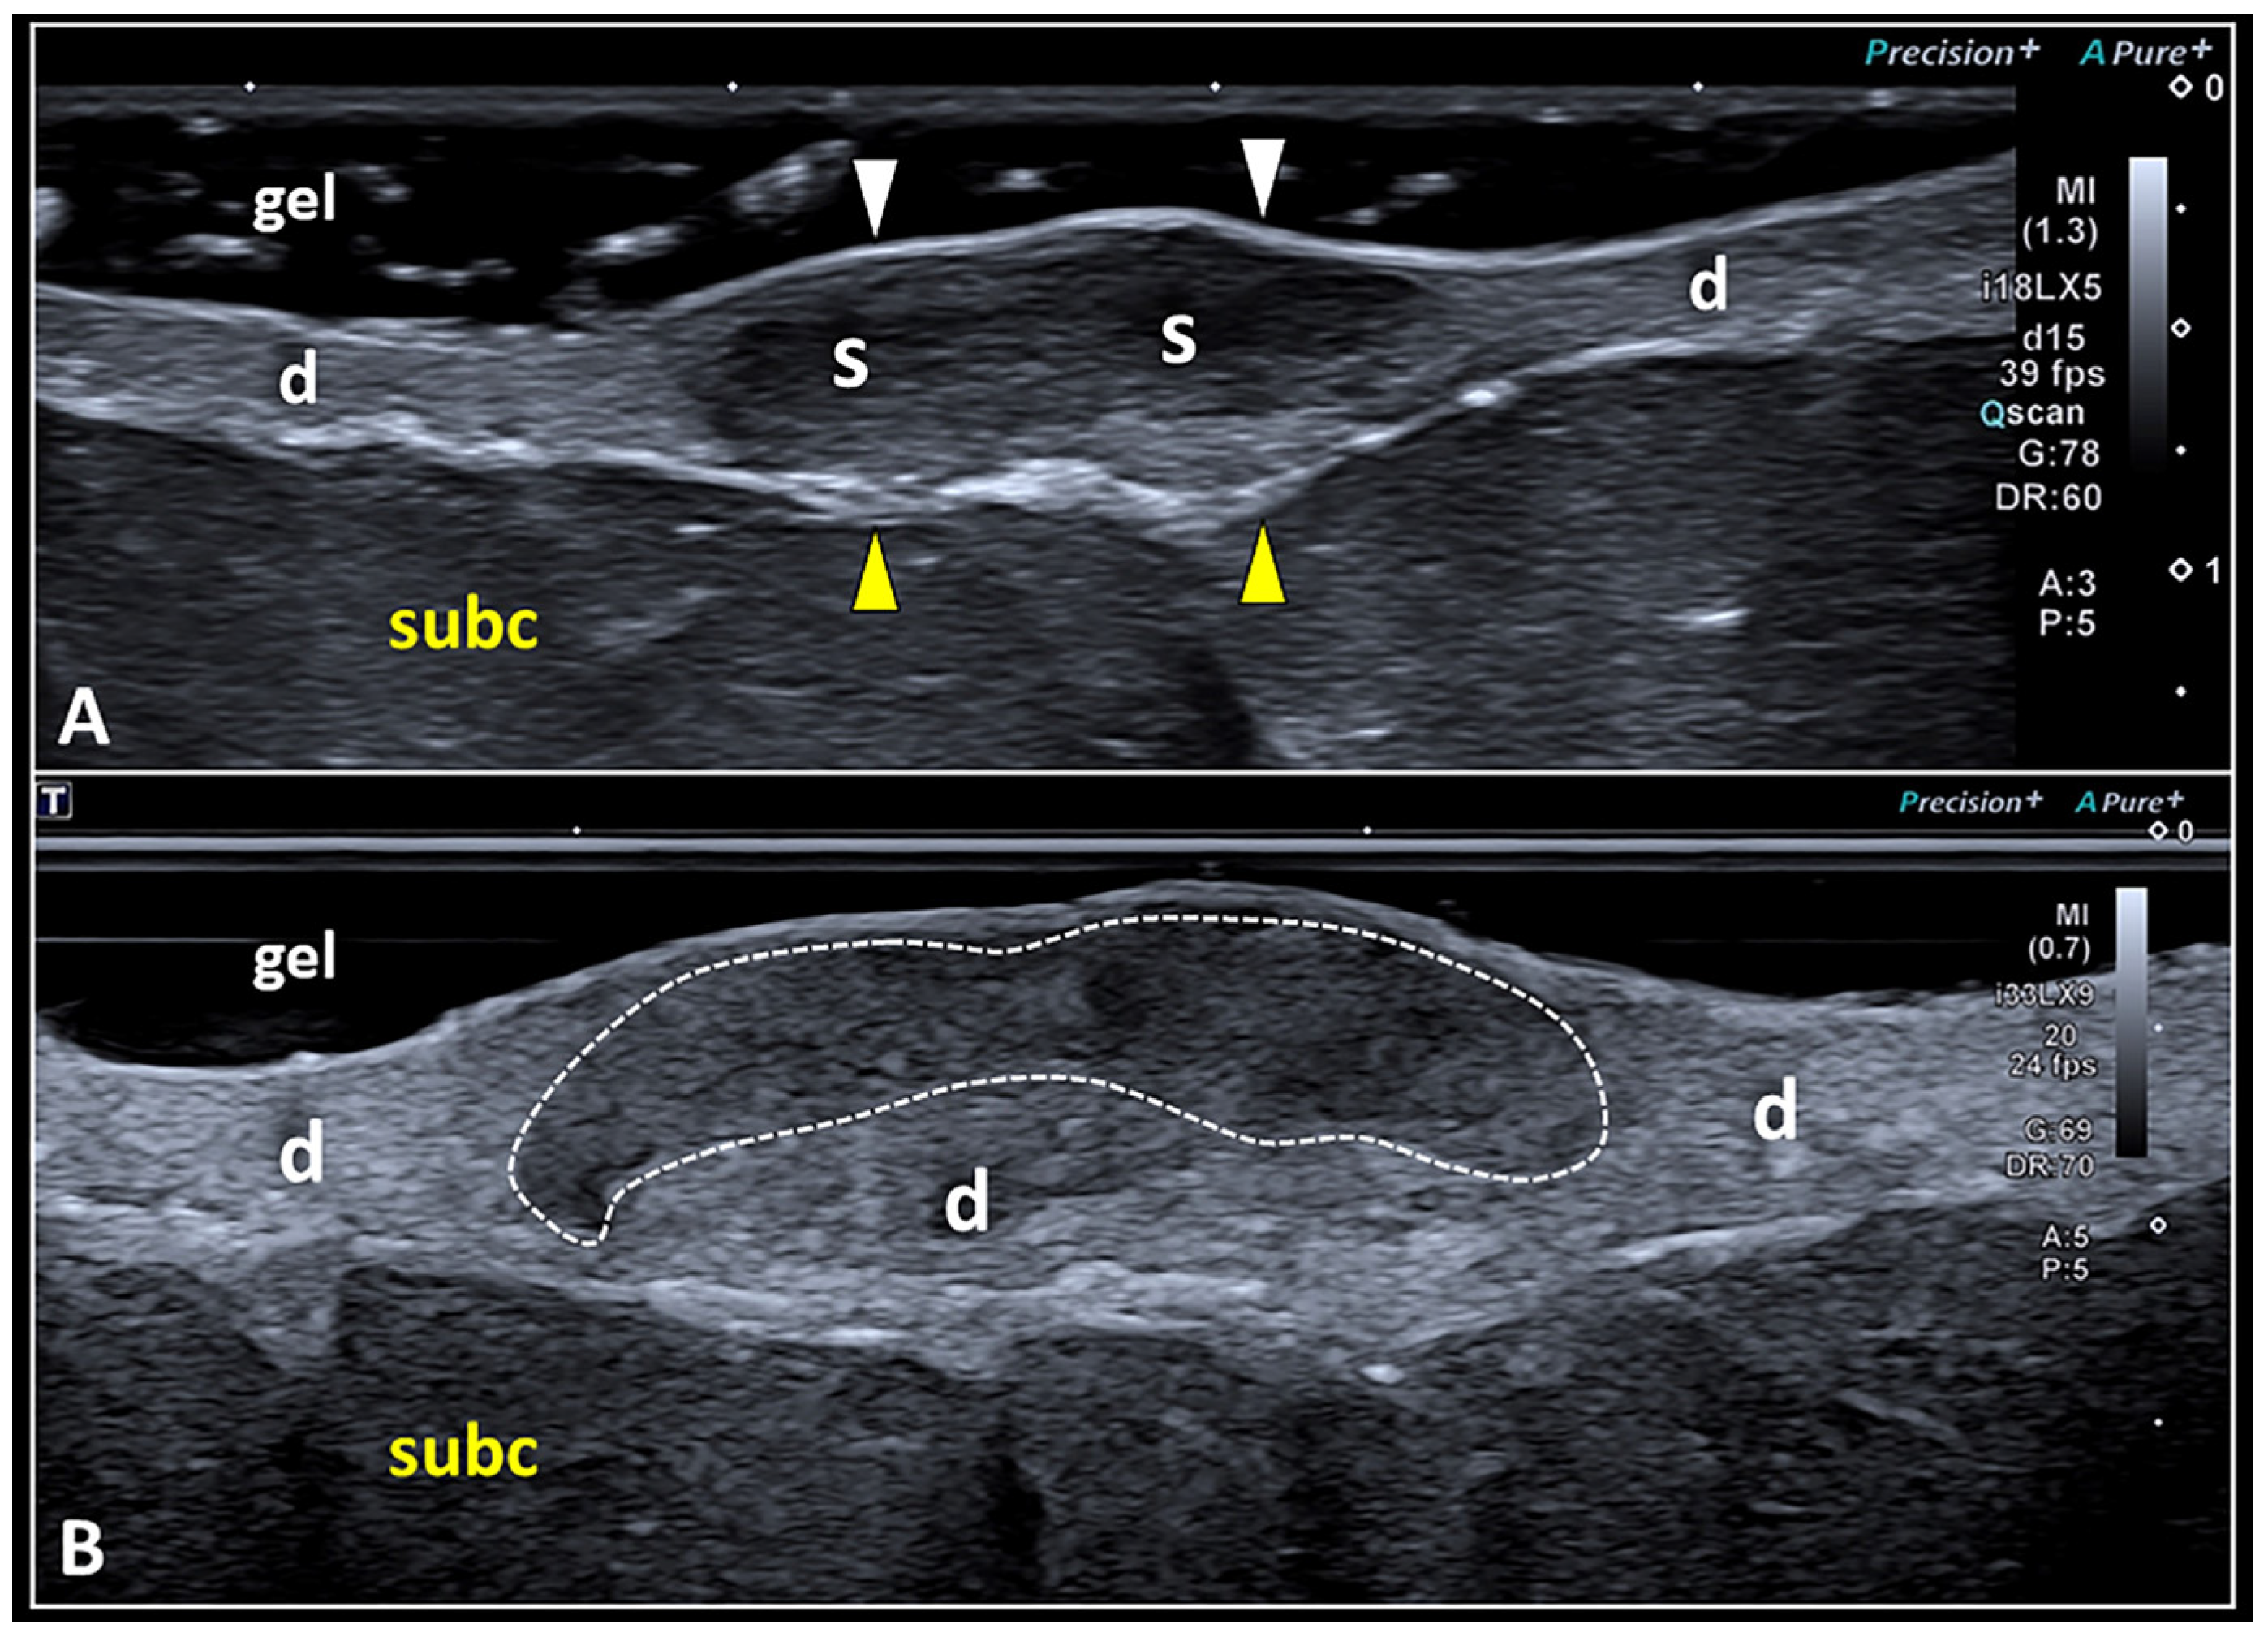

Figure 5.

High-frequency US imaging of SSs. Hypoechoic scarring tissue (S) may involve the dermis (d) in its entire thickness, displacing the overlying epidermis (white arrowheads) and the underlying dermo-hypodermal interface (yellow arrowheads) (A). Using the very high-frequency transducer, a scar (white dotted line) selectively involving the most superficial portion of the dermis (d) and preserving its deep component can be visualized using the suspension technique (B). subc: subcutaneous tissue.

As previously mentioned, despite the high concentration of collagen fibers inside the scar that generate additional acoustic interfaces compared with the physiological dermis, it is paradoxically hypoechoic [7]. This unexpected sonographic texture seems to be related to the presence of water molecules bound to the glycosaminoglycans and proteoglycans, and the fluids widely distributed inside the extracellular matrix of skin scars [7,32,33]. Nowadays, high-frequency US transducers allow a very detailed evaluation of the spatial location of the skin scar within the dermis [34]. Indeed, the fibrotic tissue can involve the entire thickness of the dermal layer or can selectively involve its superficial or deep portion (Figure 5).

Figure 6.

Pitfalls in Doppler imaging of SS. Using a large amount of gel (i.e., the suspension technique) and fully including the scarring tissue (S) inside the Doppler box, it is paramount to accurately differentiate the real vascular signals (white arrowhead) inside the scar (A) from the ‘fake’ ones (yellow arrowheads) generated by the acoustic interface between the epidermis and the gel (B). d: dermis, subc: subcutaneous tissue.

Likewise, artifactual flow signals at the gel–epidermis interface should not be misinterpreted as real vascular signals of the scarring tissue [27]. Indeed, fake vascular signals generated at the acoustic interface between the two different histological compartments are quite frequent during the musculoskeletal US and can be considered as a pitfall, especially for beginners. In this sense, minor shifts of the transducer over the target area or tiny changes in the pressure applied over the gel pad are very often tricks sufficient to promote the disappearance of these artifacts.